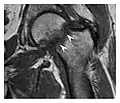

a

b

c

Figure 8: Proximal diaphyseal fatigue fracture of the tibia in a 20-year-old man with a history of regular jogging. (a) Lateral radiograph shows no obvious fracture lines but a subtle localized medial tibial cortex periosteal reaction (arrows). (b) Sagittal reformatted CT image acquired 1-month after the radiograph shows a linear hypoattenuation in the tibial cortex (arrowhead), as well as obvious periosteal thickening (arrows). (c) Sagittal T2-weighted fat-saturated image acquired the same day shows an area of hyperintensity spreading over the proximal tibia (arrows), which is consistent with the presence of proximal tibial fracture.[1]